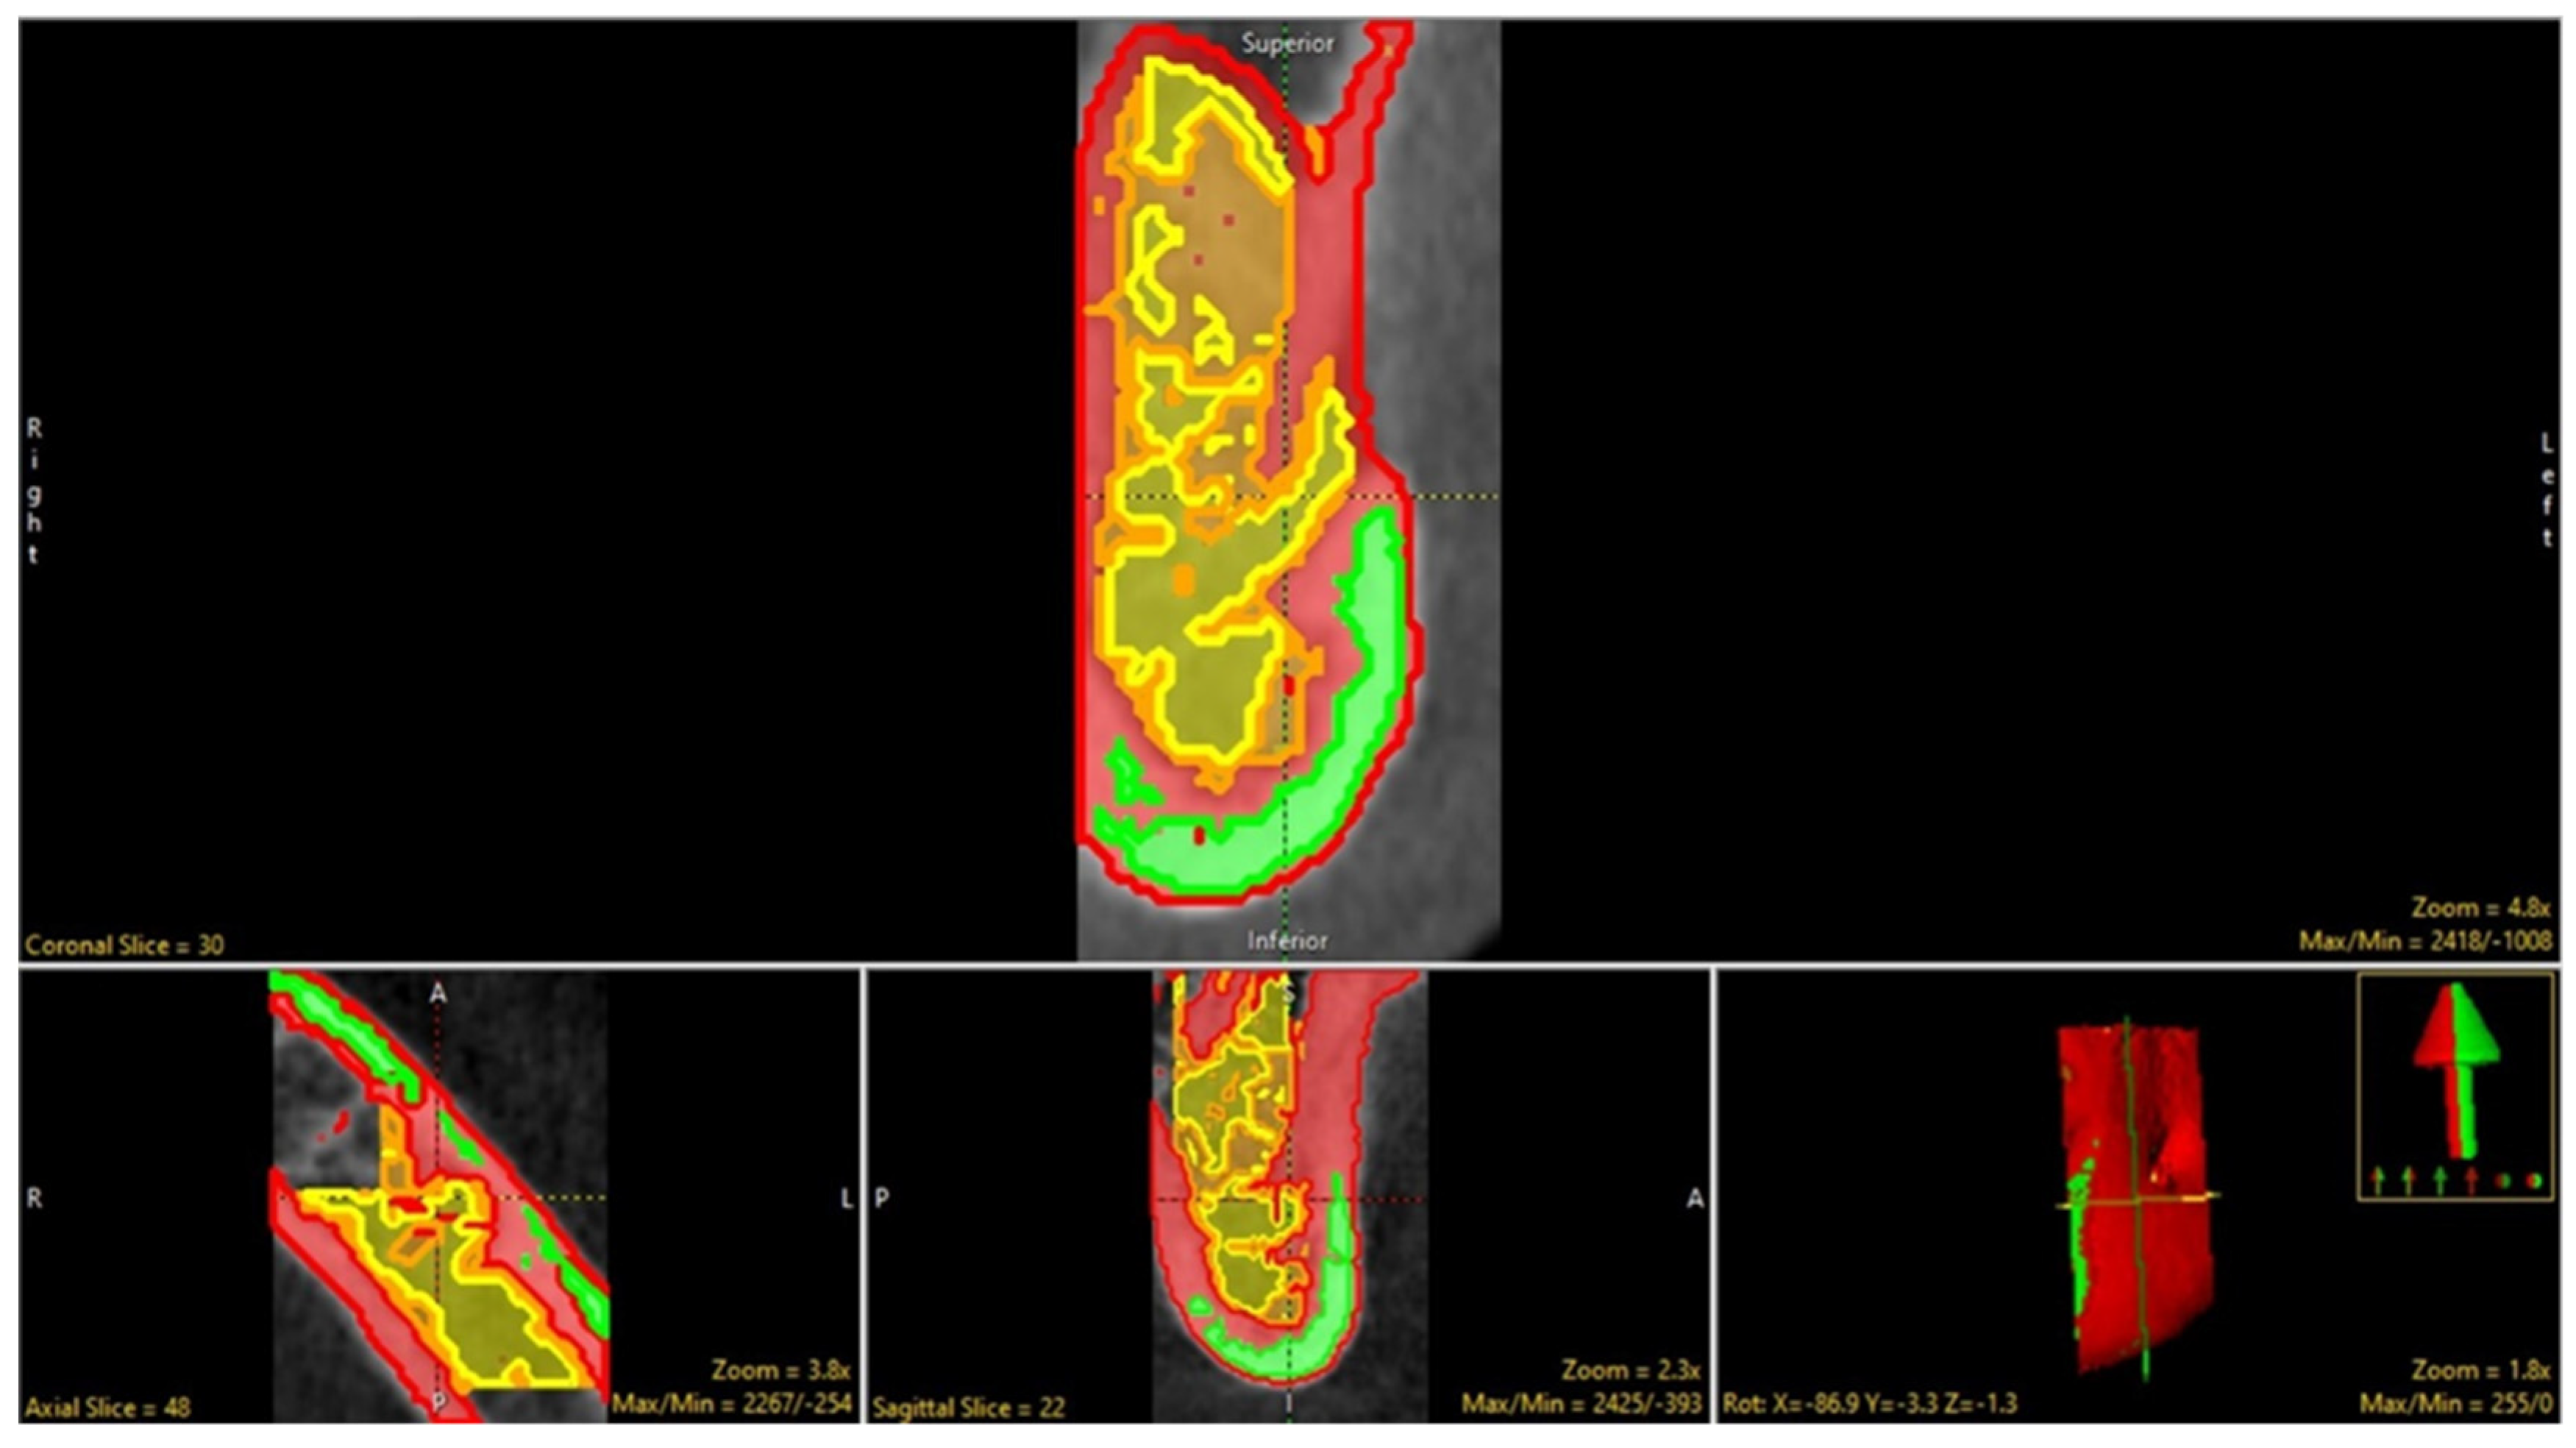

2.1. Selection of Region of Interest (ROI)

2.2. Data Preprocessing

2.3. Segmentation (Manual and Semi-Automatic)